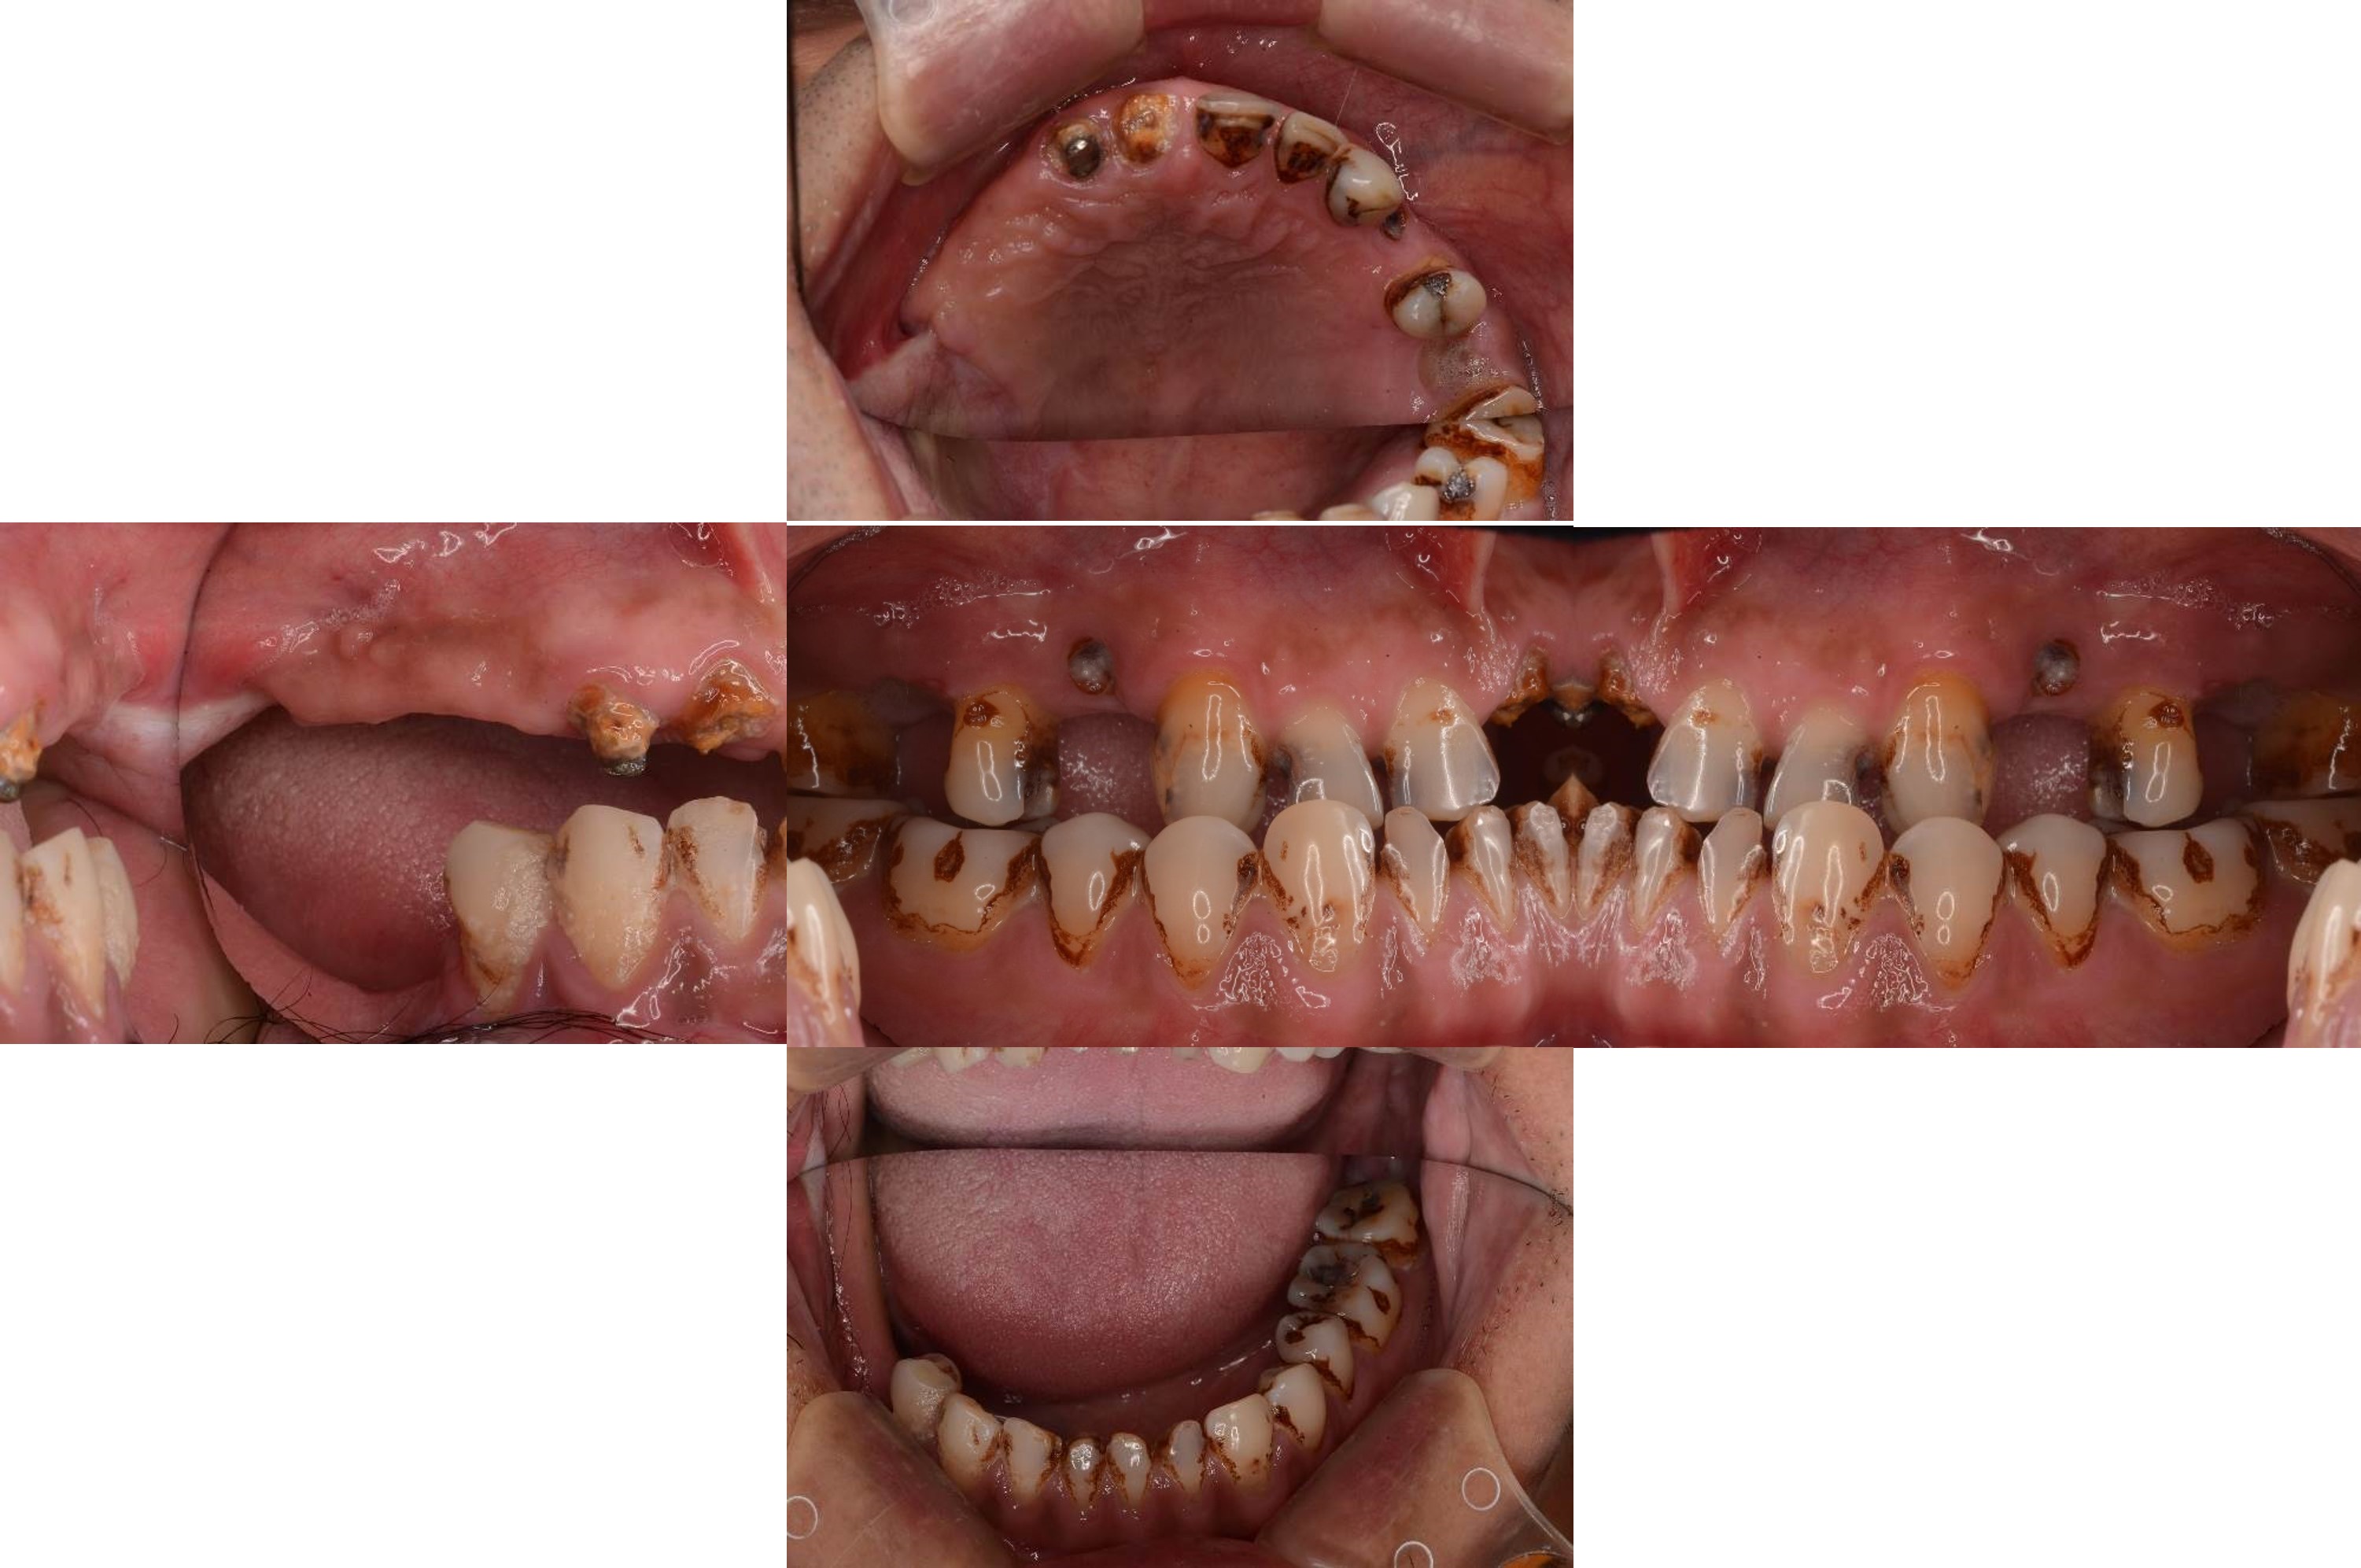

治療前,咬合喪失,磨耗

治療前,殘根與牙周支撐不良

模型咬合分析

蠟型模擬最終可能成果